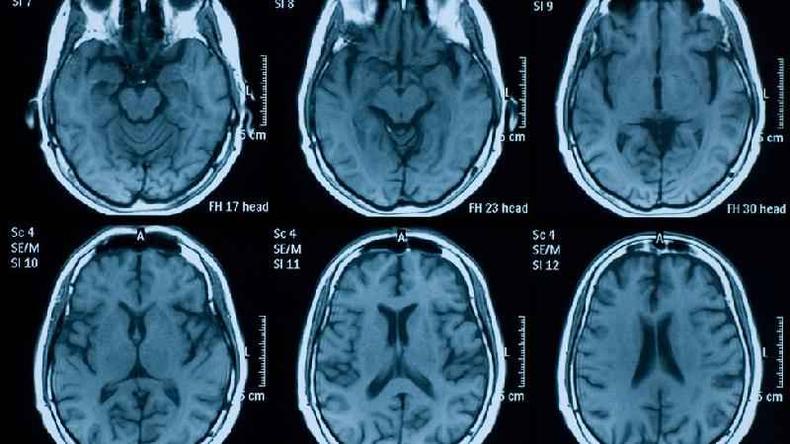

"Por meio de exames de imagem de pessoas socialmente isoladas, detectamos mudan�as no volume das regi�es temporal, frontal, occipital e subcortical, assim como no hipocampo e na am�gdala", conta Sahakian � BBC News Mundo.

Em 2018, por exemplo, um estudo publicado na revista cient�fica Neurology, da Academia Americana de Neurologia, mostrou que um alto n�vel de cortisol em pacientes estava associado a uma mem�ria e percep��o visual pior, assim como a volumes mais baixos de massa cinzenta total, occipital e do lobo frontal.